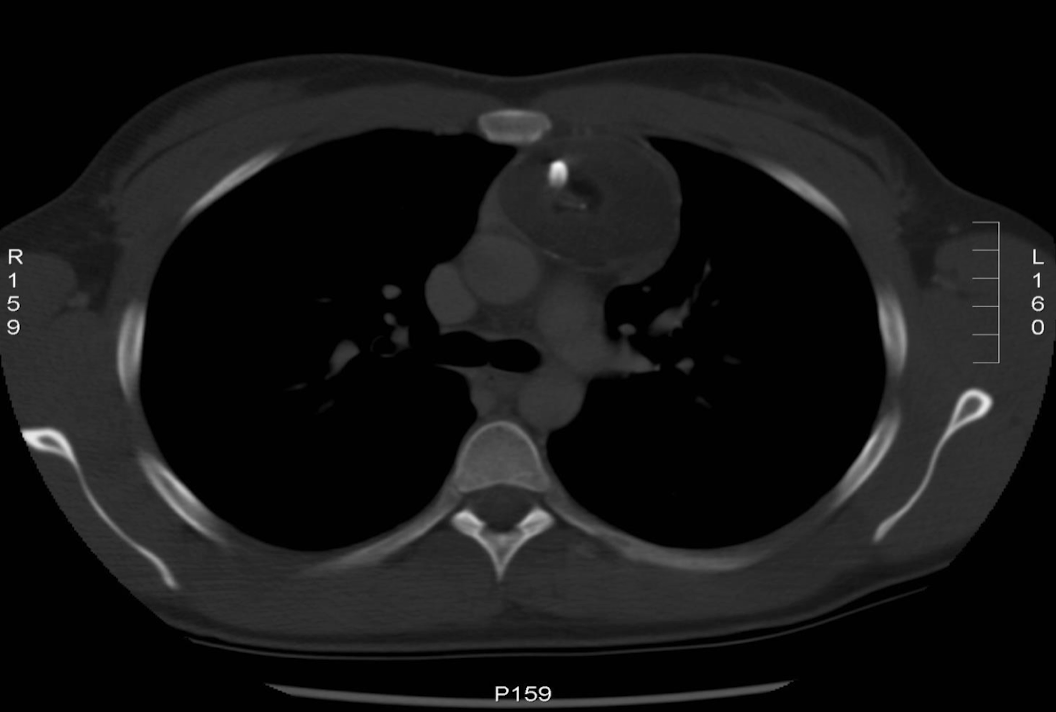

<p>When do we need a bone window for a thorax scan?</p>

When do we need a bone window for a thorax scan?

Requested if pt has suffered any trauma or if looking for calcifications

<p>Requested if pt has suffered any trauma or if looking for calcifications </p>

What can we see in a mediastinal window for a thorax scan that we can’t see in a lung scan?

Pulmonary artery